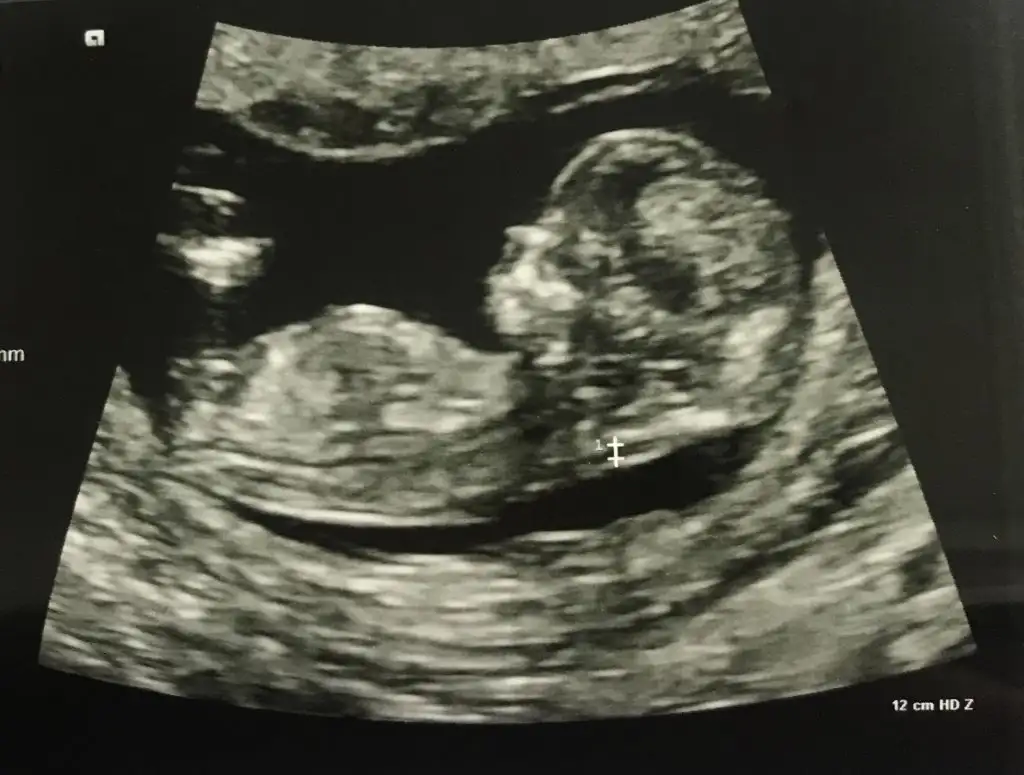

Kıza benzettimEki Görüntüle 2710264 banada tahmin yaparmisiniz lütfen![]()

Eki Görüntüle 2710264 banada tahmin yaparmisiniz lütfen![]()

Canım senin bebiş erkeğe benziyorEki Görüntüle 2710264 banada tahmin yaparmisiniz lütfen![]()